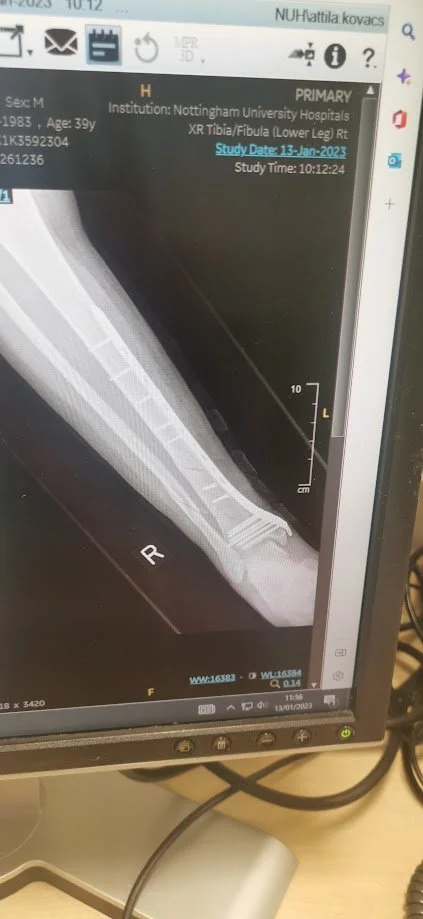

When going for short walk and taking some photographs of sunset changes into different kind of adventure. One wrong step, little slip on the grass, and one loud crack ended of our Cornwall adventure.